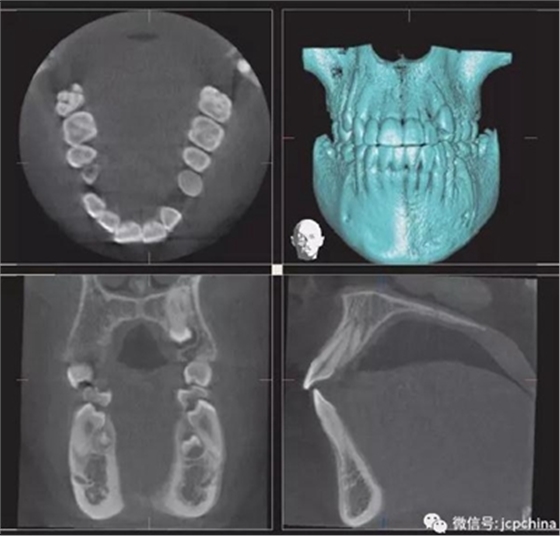

(2)射線硬化偽影

當(dāng)投射線的低能量光子被大量過濾時(shí)(如口腔銀汞),使透射過的剩余光子平均能量非常高,當(dāng)反投射時(shí),就會(huì)出現(xiàn)條狀偽影。由于口腔修復(fù)材料的阻射性質(zhì),因而射線硬化偽影非常常見。

(a)根尖片。

(b)CBCT矢狀面。

同一解剖位置顯示出的廣泛射線硬化偽影,使CBCT分辨金屬邊緣變得困難。CBCT圖像中27牙的近中壁缺損可能為齲損(紅色箭頭),而根尖片(黃色箭頭)卻顯示正常。